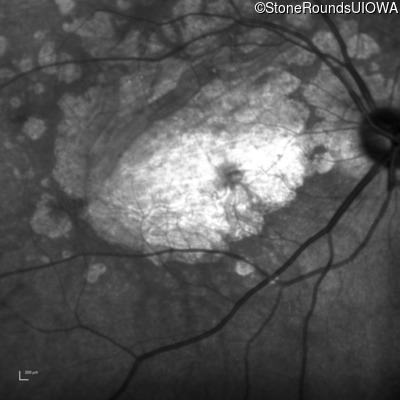

Infrared Fundus Photograph - Right - 10/300

Exemplar